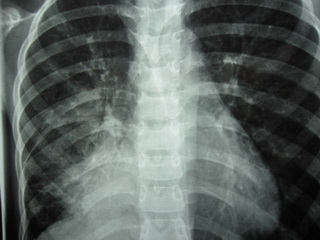

بيمار پسر 13 ساله با شكايت تب و درد همي توراكس راست مراجعه كرده

است.

:PIمشكلات

بيمار از حدود يكماه قبل از مراجعه با درد كشاله ران سمت چپ بدون سابقه تروما شروع

شده است كه همراه با تب و كاهش وزن بوده است. بيمار جهت بررسي در مركز درماني ديگر

بستري و به دنبال گرفتن راديوگرافي ريه متوجه

Consolidation

در ناحيه پاراكاردياك راست شده است و تحت درمان آنتي بيوتيك تزريقي

به مدت 2 هفته قرار گرفته و به علت عدم پاسخ درماني مناسب جهت بررسي بيشتر به اين

مركز ارجاع شد.

Chest X Ray

Report of Spiral

HRCT of Chest without contrast media

A

right paracardiac soft tissue is noted, with some area of air bronchogram and

consolidation pattern at the center of the lesion which has mass like appearance

At the periphery of the mass some lymphangiectasia also seen and right hilum

prominency